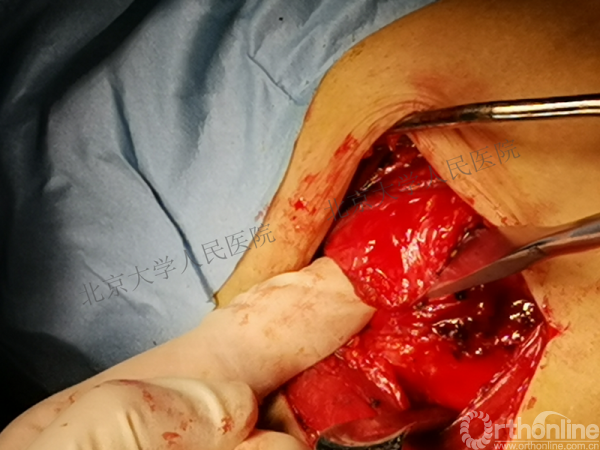

全麻下行切开复位内固定术,备植骨+关节镜检

胸大肌三角肌间隙入路

操作步骤

(二)改良McLaughlin手术

2.将肱骨小结节连同其附着的肩胛下肌同时内移固定,能够获得更好的骨性愈合以及稳定性

3.缺损范围:20%~40%

4.优点:更好的骨性填充,更安全的肩胛下肌腱止点重建